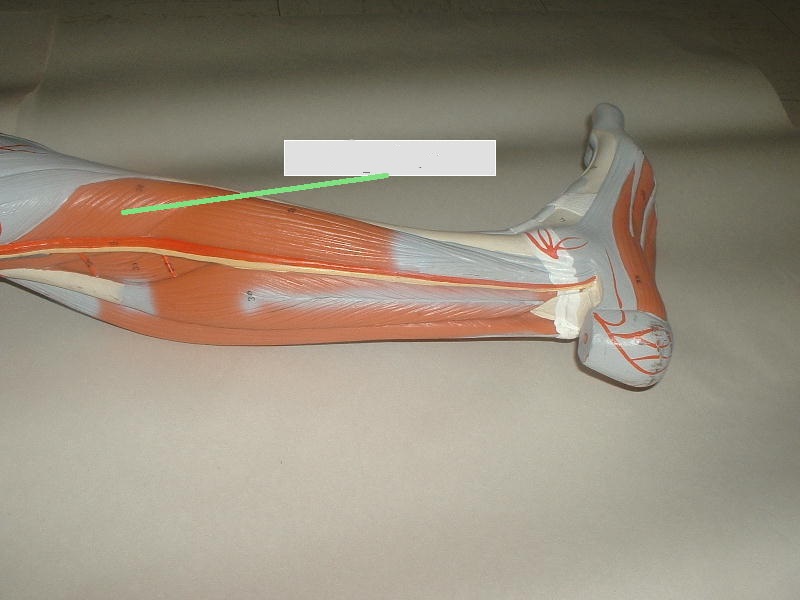

Анатомия мышцы Palmaris Longus